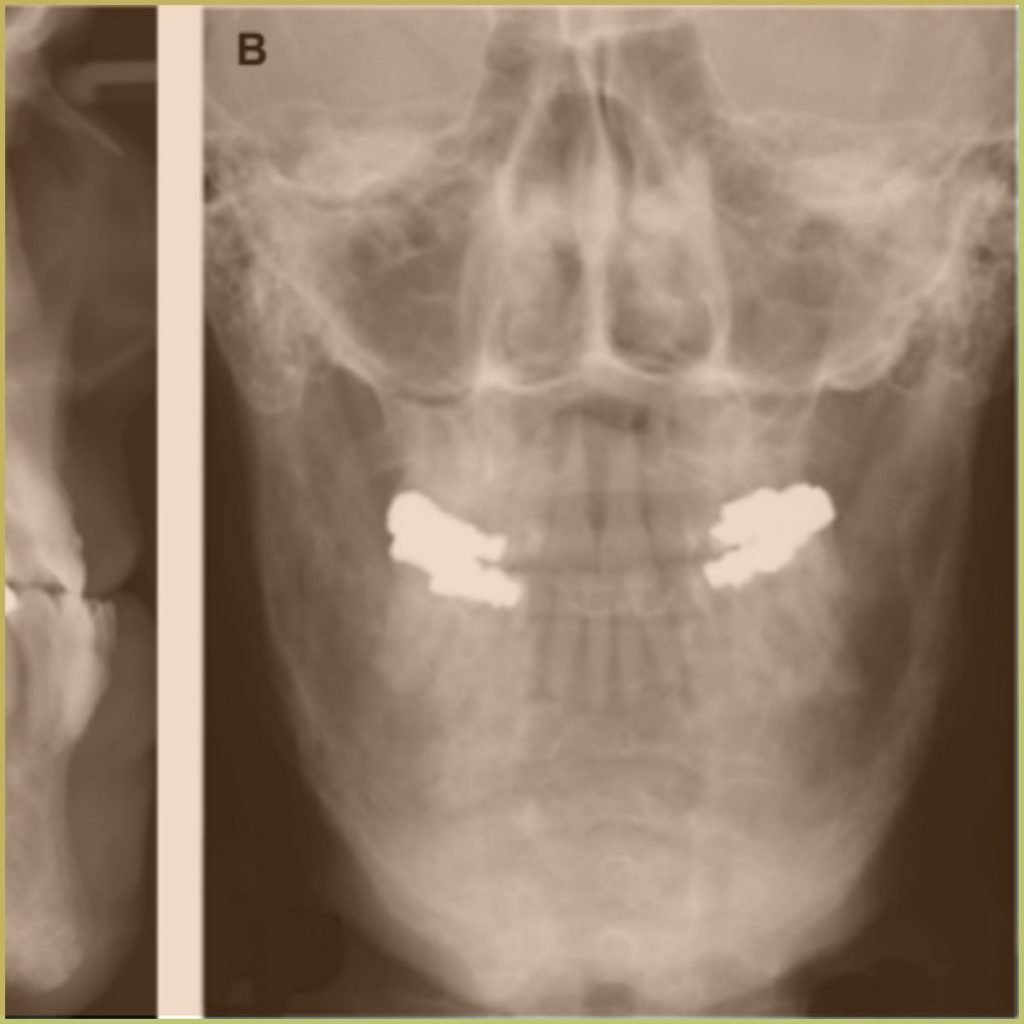

CEMENTO-OSSEOUS DYSPLASIA

Florid Cemento-osseous Dysplasia is a asymptomatic non-neoplastic fibro-osseous lesion that originates from the periodontal membrane and presents as multi-quadrant radiopaque cementum-like masses. The cause is unknown. The common clinical presentation includes:

- Radiopaque masses within peripheral radiolucent rim.

- Becomes more radiopaque with age.

- Lamina dura is usually absent.

- Most commonly located in the mandibular anterior region.

- May involve apices of one or more vital teeth.

- Noted usually in fourth and fifth decades.

Diagnosis is based on the lesion history and clinical presentation only. A biopsy is usually not recommended due to the risk of severe infection, bone sequestration and osteomyelitis. Your differential diagnosis should include:

- Multiple periapical abscesses (vitality testing essential).

- Florid osseous dysplasia.

No treatment is required.